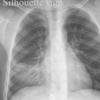

Silhouette sign

RML collapse